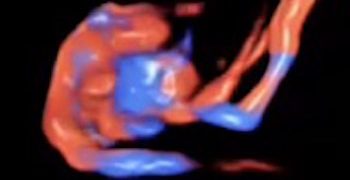

How To Do Gennaio 2021: Ecografia nelle Lacerazioni Ostetriche dello Sfintere Anale

Cari soci, il 2021 si apre con un interessante video "How to do", sul ruolo dell'ecografia nella diagnosi delle lacerazioni ostetriche dello sfintere anale. Grazie a Federica Bellussi! Il video...